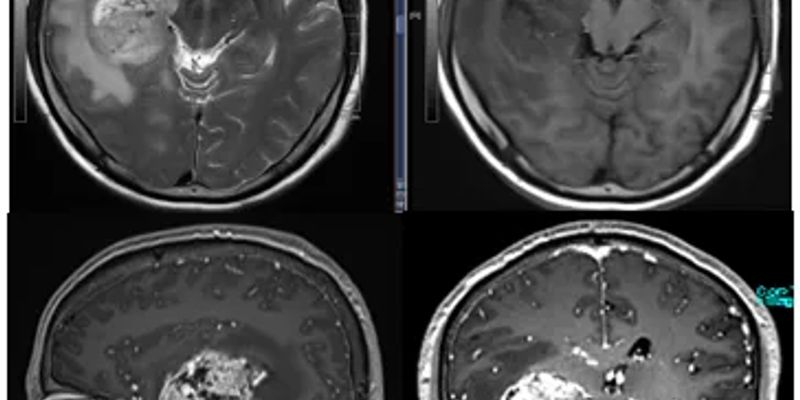

图:靶区范围的定义与划分

- 实验组: 采用创新的HSIB-IMRT(中等分割同步增剂量调强放疗)方案。研究人员利用多模态MRI和弥散张量成像(DTI)技术,精准识别肿瘤的浸润路径,从而制定个体化的、更小的放疗靶区(CTV)。

- 对照组: 采用传统的RTOG标准方案,即在肿瘤病灶基础上进行均匀的2cm外扩,照射范围更广。

- 显著缩小的放疗靶区: 实验组的放疗靶区体积(CTV)中位数显著小于对照组(174.4 cm³ vs 225.0 cm³),靶区体积成功缩减了约22.5%。这意味着实验组患者有更多的正常脑组织免受了不必要的放射损伤。